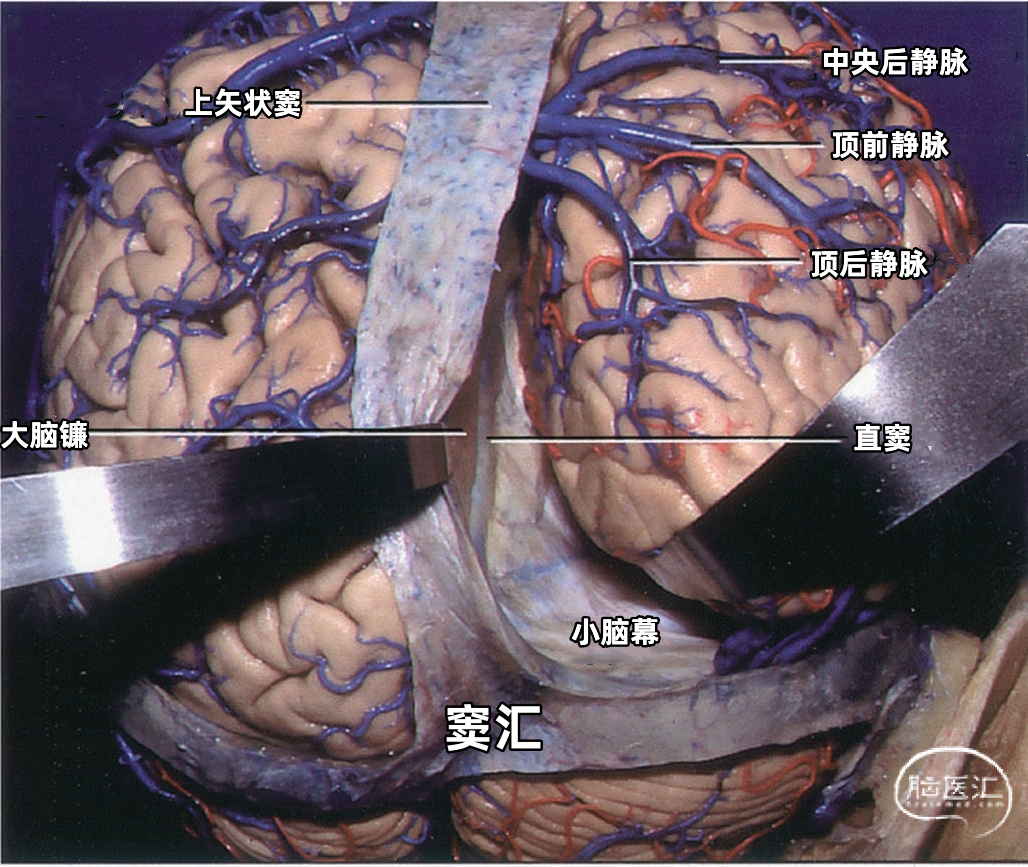

▼6.直窦

直窦(straight sinus)位于大脑镰与小脑幕的连接处(下图),起源于胼胝体压部后方,由下矢状窦与大脑大静脉(Galen静脉)汇合而成,汇合处管径膨大,向后于枕内隆凸处注入窦汇。直窦平均长约50mm,呈尖端向上的三角形。此窦多数是下矢状窦的直接延续。大脑大静脉是汇入直窦的最大静脉。直窦向后除注入窦汇外,尚可直接注入横窦,它可以进入任何一侧的横窦,但多数主要汇入左侧的横窦。

▼7.窦汇

窦汇(confluence of sinuses)位于枕内隆凸平面,正中线稍偏右侧,相当于人字缝尖至枕骨大孔后唇的中点处。通常由上矢状窦与直窦在枕内隆凸处汇合而成。向左、右两侧汇入横窦。 上矢状窦和直窦的汇合方式颇多,窦汇的延续情况也各有差异。上矢状窦、直窦汇入右侧横窦者较多,约占30%。上矢状窦和直窦各分为左右支,两窦的右支合为右横窦,两窦的左支合为左横窦者占26%。而上矢状窦、直窦、枕窦及横窦汇合者占22%。▼8.横窦

横窦(transverse sinus)从枕内隆凸沿小脑幕在枕骨内侧面附着形成的浅沟向外侧走行。在岩骨嵴后方,横窦和岩上窦汇合处,横窦离开小脑幕,转向下前方,移行于乙状窦。横窦除主要收纳上矢状窦和直窦的血液外,还收纳大脑下静脉、小脑下静脉、脑干静脉、板障静脉和导静脉的血液。横窦可通过枕骨的导静脉与颅外静脉相通。 横窦于枕内隆凸附近的起点变化颇多,可以起自窦汇,也可起自上矢状窦或直窦(上图)。 上矢状窦可平均回流入左右两侧横窦,或一侧为主,或完全一侧。 右侧横窦通常较大,并接受上矢状窦的大部分引流(上图)。左侧横窦较小,主要接受直窦引流。所以,右侧的横窦、乙状窦和颈内静脉的血液主要来自大脑的浅部结构,左侧的横窦、乙状窦和颈内静脉内的血液主要来自大脑内静脉、基底静脉和大脑大静脉引流的深部结构。每侧的引流差异导致一侧或另一侧静脉回流受阻产生不同的临床症状,且左侧或右侧颈内静脉压迫产生不同的Queckenstedt's奎肯征。